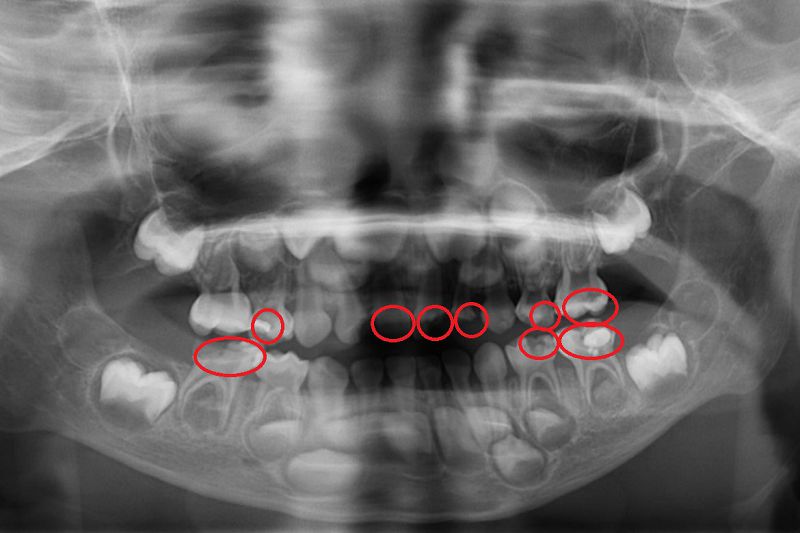

4. 定期至牙科檢查:雖然學校會定期塗氟,但礙於環境及燈光,執行醫師未必每次都能清楚檢查牙齒狀況,因此即使孩子沒有牙痛或明顯異常,也應至少每半年至專業的兒童牙科進行檢查,以利及早發現肉眼難以察覺的齲齒。